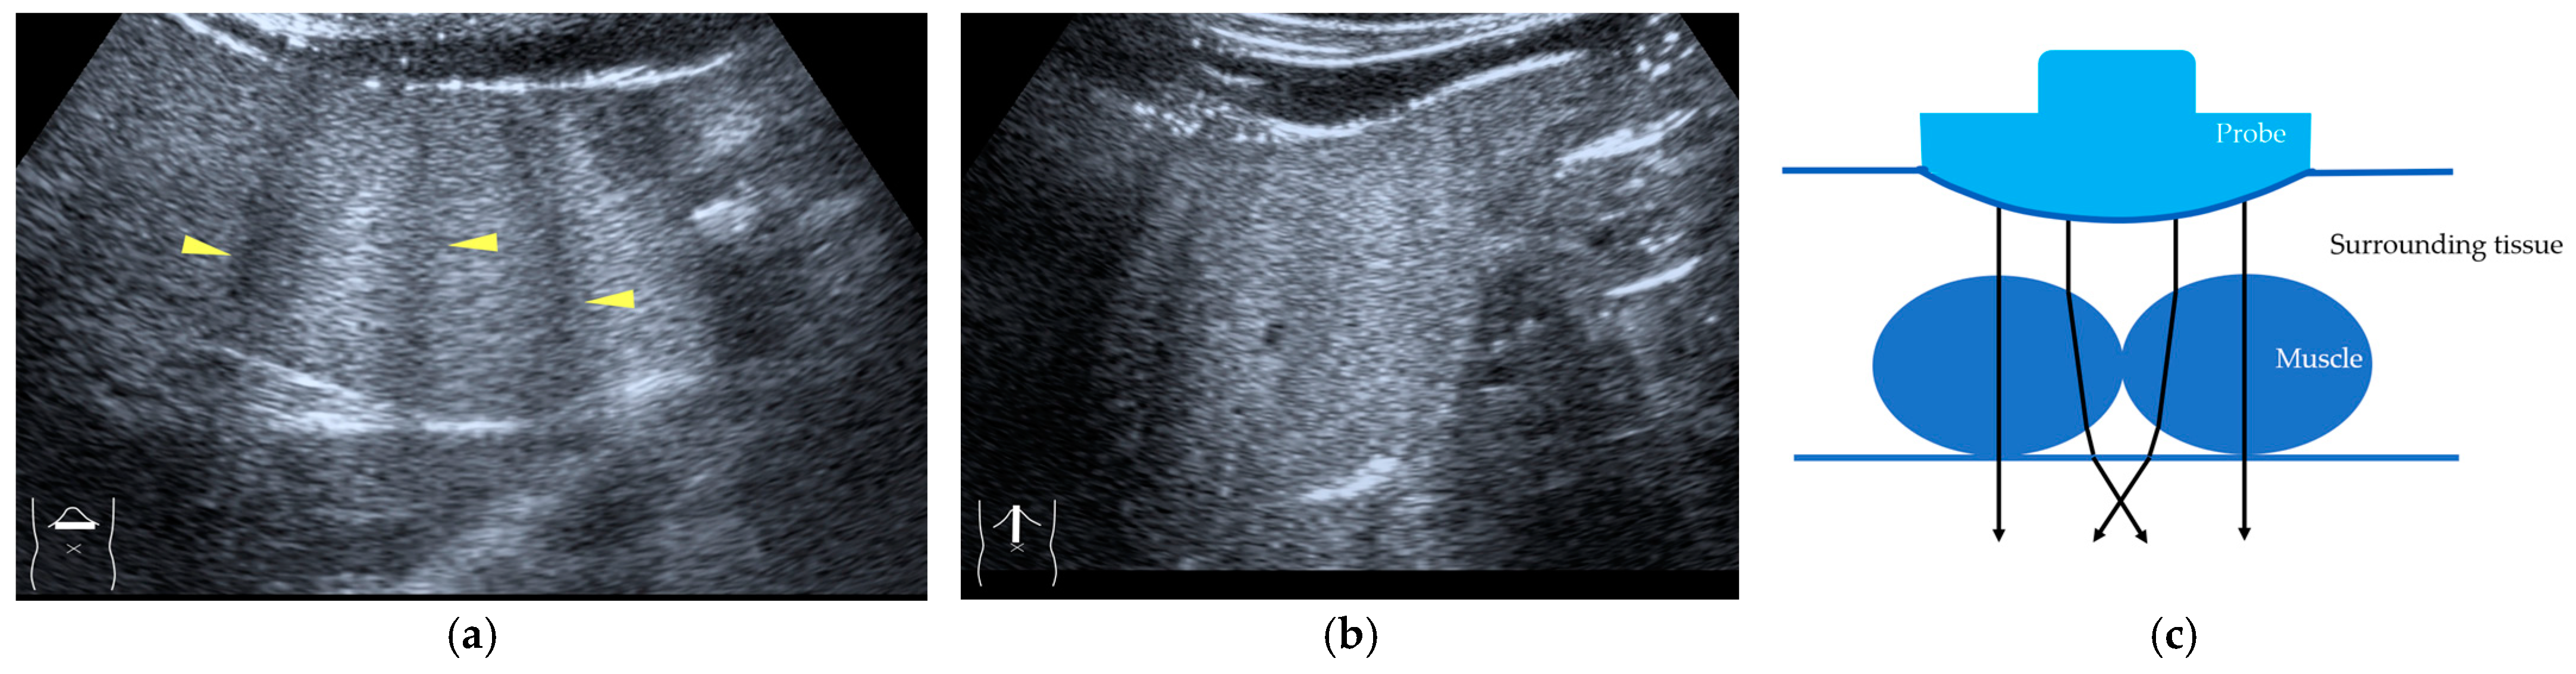

3.2.3. CEUS-Related Posterior Echo Enhancement

CEUS-related posterior echo enhancement (PEE) differs from that of B-mode US. PEE is the most easily recognizable US artifact, and it is characterized by an echogenic band behind a lesion with sonographically different characteristics. In B-mode US, PEE is thought to be secondary to changes in the attenuation of US beams. The area distal to a less attenuating lesion exhibits an increased US intensity and is brighter than it would be without the lesion [60,61]. Posterior echoes are also considered to be strongly related to sound refraction, which occurs when the US beam strikes the interface between two media with different acoustic velocities at an oblique angle of incidence [62]. Whether the US beams converge or diverge depends on the form of the interface and whether the sound path is from a high-velocity medium to a lower-velocity medium or the opposite. The latter condition is thought to give rise to PEE. Aside from these well-known causal factors, there are many other factors contributing to PEE, including reverberation. In brief, PEE remains a multifaced entity featuring complex interplay among sound attenuation, sound refraction, sound reverberation, and other factors. In the clinical setting, hemangioma [63], hepatocellular carcinoma [61], and hepatic cysts are known to cause PEE. We sometimes encounter CEUS-related PEE in daily CEUS examinations. It is characterized by the sudden appearance of a highly echoic zone during CEUS at a location where there was no highly echoic zone in B-mode US (Figure 14). Although this phenomenon’s mechanism of appearance has not been fully elucidated, the most plausible explanation is that many scattered signals emitted from the contrast agent, which rapidly flow into the lesion, interfere with each other inside the stained area, and the reflected time-delayed signals return to the transducer with a certain delay, resulting in the appearance of a highly echoic zone behind the lesion. The precise mechanism of CEUS-related PEE is a problem to be resolved in the near future.

Figure 14.

Posterior echo enhancement appearing during CEUS. (a) Gray-scale US of the case (arrows). (b) CEUS image of the lesion (focal nodular hyperplasia) (arrows). (c) CEUS image of posterior enhancement (arrow heads). Posterior echo enhancement appears immediately after the mass is rapidly and homogeneously enhanced. (d) Reasonable explanation of this phenomenon. Many scattered signals emitted from the bubbles that rapidly enter the mass lesion interfere with each other inside the stained area, and these scattered signals return to the transducer with a certain time-delay. These time-delayed signals are displayed as a PEE. Black circle: mass lesion; small blue circles: CEUS bubbles; red solid line: ultrasound beam; red dashed line: ultrasound is expected to travel; red arrows: reflection between bubbles.